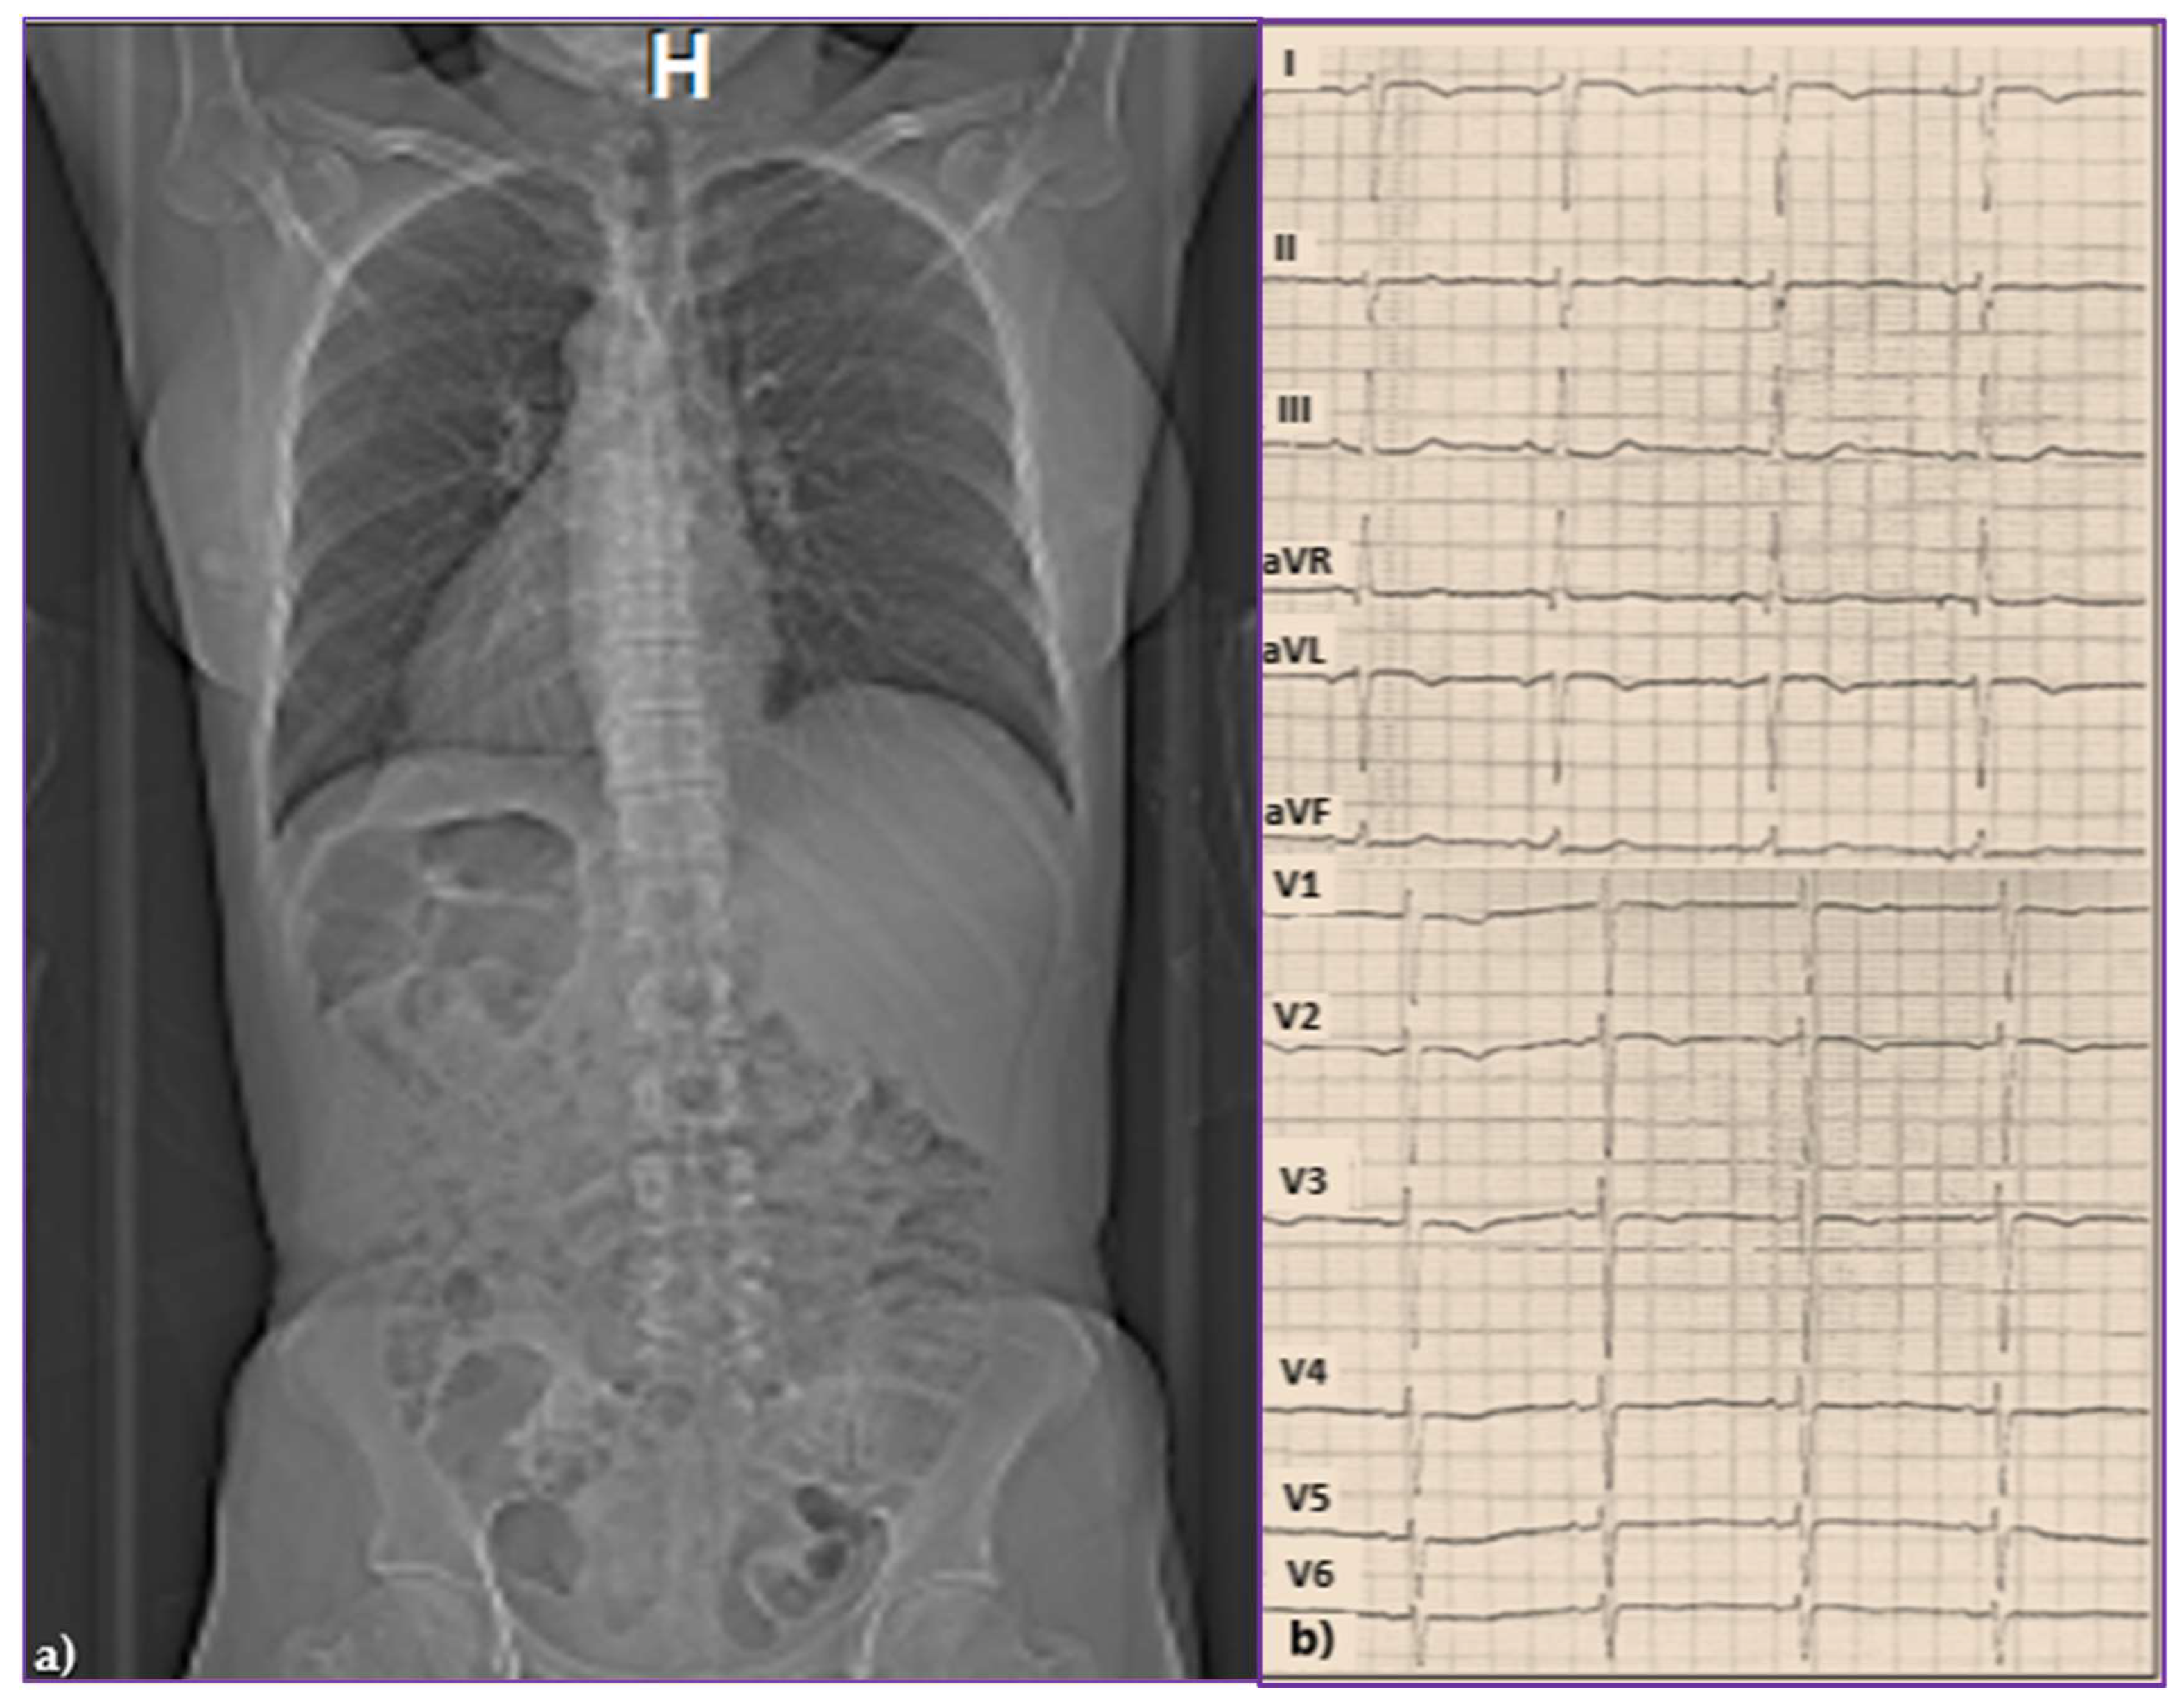

2.1. Initial Presentation

2.2. Diagnostic of SSS and Pacemaker Implantation